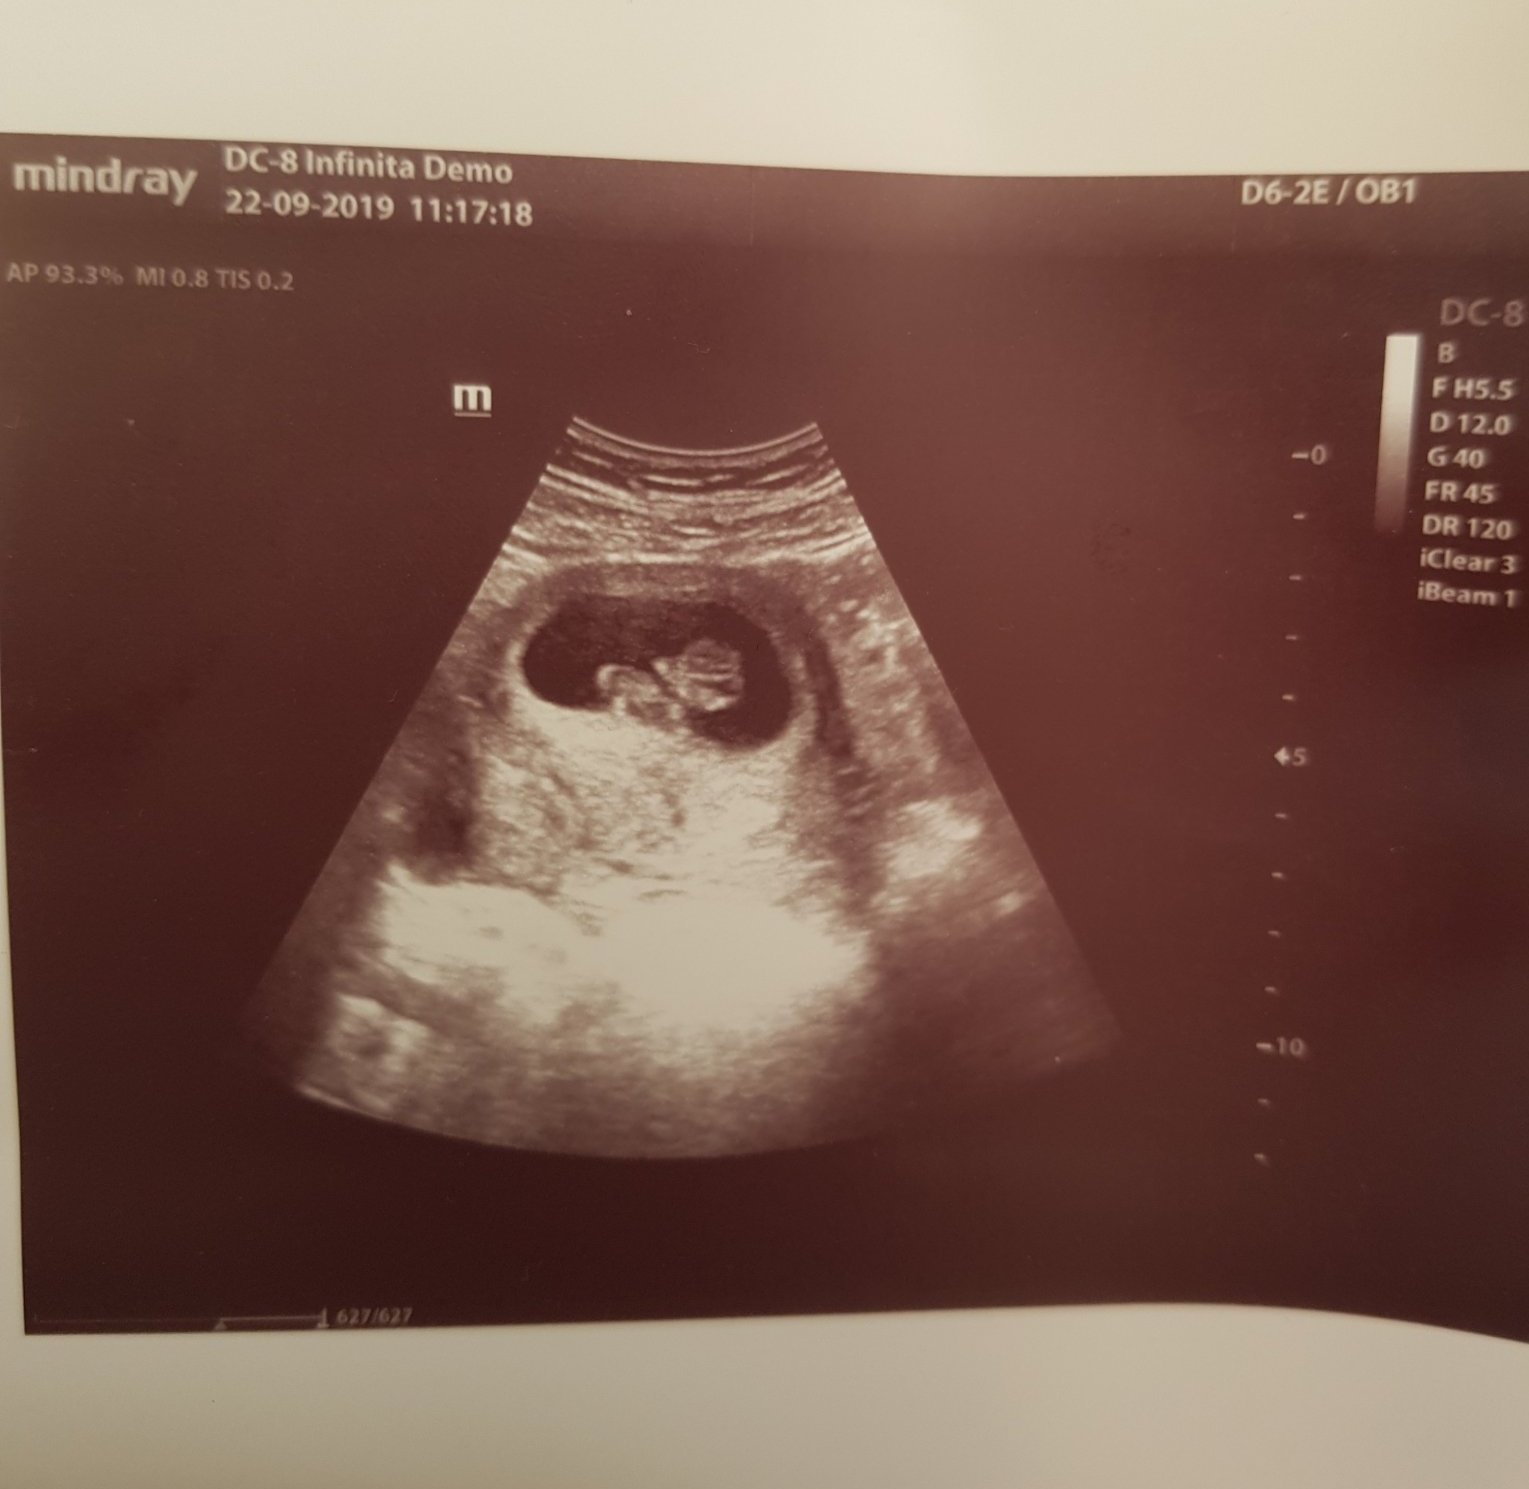

В 11с.5дни съм.Доктора всеки път ми казва,че щом няма къвене,е нормално ии да си пия но шпа.На преглед съм след седмица и ще изкукам до тогава.